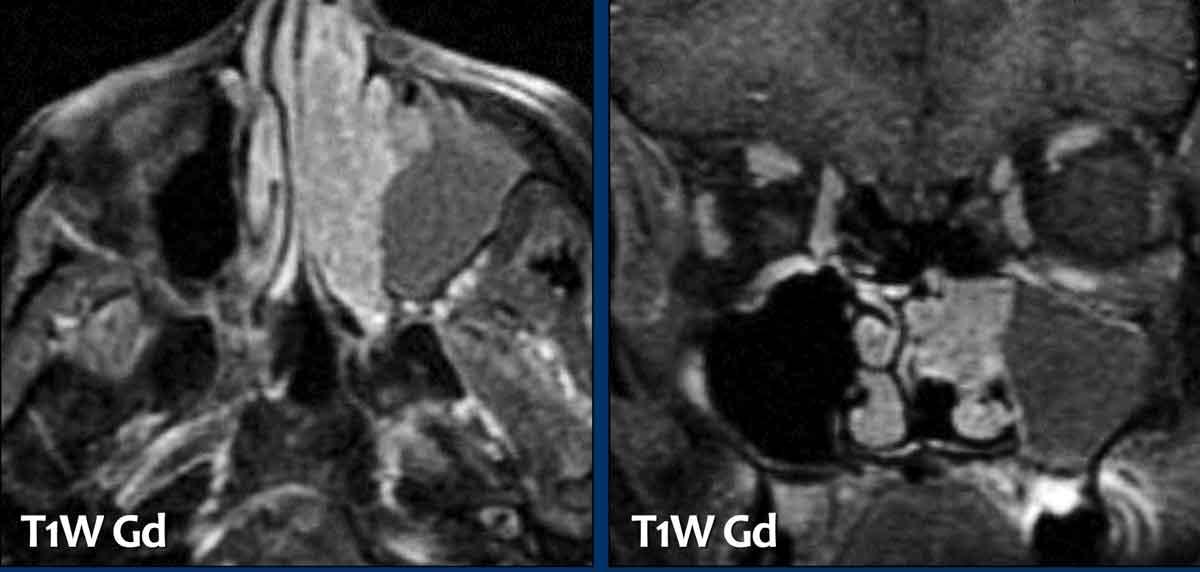

U cơ vân (Rhabdomyosarcoma)

Các hình ảnh này của một bệnh nhân nam 16 tuổi với biểu hiện lồi mắt và chảy máu mũi.

Dựa trên kết quả CT tại bệnh viện khác, có nghi ngờ u xơ mạch máu vị thành niên (juvenile angiofibroma) — một khối u tăng sinh mạch máu, xâm lấn tại chỗ, gặp ở nam giới trẻ tuổi với biểu hiện chảy máu mũi nặng, có thể đe dọa tính mạng.

Trên các hình ảnh này, có một tổn thương phá hủy xương với xâm lấn vào hốc mắt.

U xơ mạch máu vị thành niên luôn xuất phát từ hốc mũi phía sau và có tâm tổn thương xung quanh lỗ bướm khẩu cái và hố chân bướm khẩu cái.

Tiếp tục xem các hình ảnh MRI…

MRI cho thấy một khối u phá hủy một bên với hạn chế khuếch tán rõ rệt (giảm tín hiệu trên bản đồ ADC).

Như vậy, chúng ta có ba dấu hiệu cảnh báo.

Hạn chế khuếch tán là một lập luận khác chống lại chẩn đoán u xơ mạch máu vị thành niên, vì một tổn thương mạch máu sẽ không gây ra hạn chế khuếch tán.

Có xâm lấn vào hốc mắt và cả vào phần mềm phía trước của má (mũi tên).

Sinh thiết được thực hiện và cho kết quả là u cơ vân (rhabdomyosarcoma), được điều trị bằng hóa trị liệu.